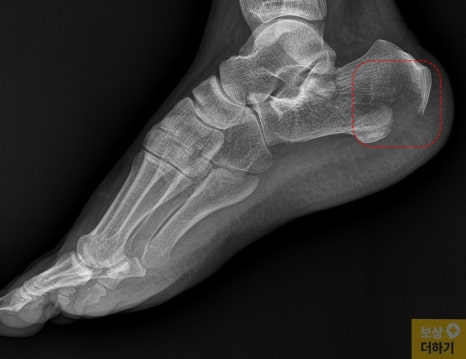

응급실에서 X-ray와 CT 정밀 검사를 진행한 결과, 우측 종골 분쇄골절이 확인되었습니다. 영상 자료(CT, X-ray)를 보시면 종골 부위가 심하게 함몰된 것을 확인할 수 있는데요.